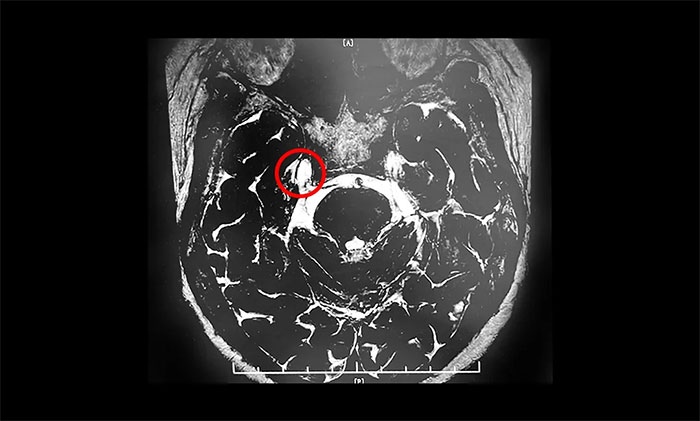

外科手术方式有多种,包括经皮三叉神经半月神经节射频温控热凝术、Meckel's囊球囊压迫术、Meckel's 囊甘油注射、伽马刀治疗及微血管减压手术。共识指出,微血管减压术的远期预后优于其他外科方法。

微血管减压术是现代神经外科典型的微创手术之一,仅通过患者耳后发际内4-5cm的切口,于显微镜下探查三叉神经走行区,将所有可能产生压迫的血管、蛛网膜条索都“松解”开,并将这些血管以Tefflon垫片与神经根隔离。一旦责任血管被隔离,产生刺激的根源就消失了,三叉神经核的高兴奋性就会随之消失,恢复正常。绝大多数患者术后疼痛立即消失,并保留正常的面部感觉和功能,不影响生活质量。